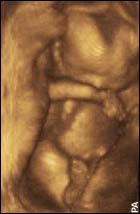

11 weeks